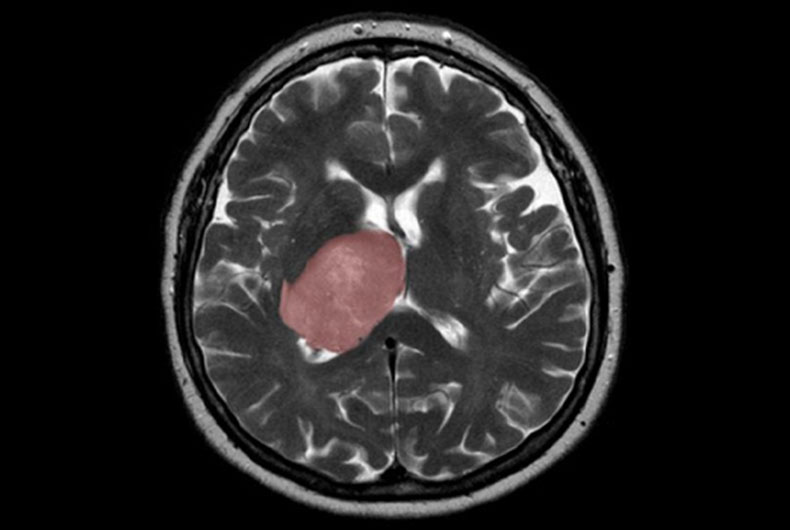

New Delhi: The cancer-causing virus Epstein Barr Virus (EBV) can infect the neuronal cells and drive various changes in biomolecules such as fatty acids, carbohydrates, and protein components, leading to diseases of the central nervous system as well as brain cancer, scientists have found.

The EBV virus has been found to be widely present in the human population. It usually does not cause any harm, but the virus gets reactivated inside the body in some unusual conditions like immunological stress or immunocompetence. This may further lead to various complications like a type of blood cancer called Burkitt's lymphoma, stomach cancer, and multiple sclerosis.

Earlier, studies provided links of EBV involvement in various neurodegenerative diseases. However, how this virus can affect the cells of the brain and manipulate them is still unexplored.